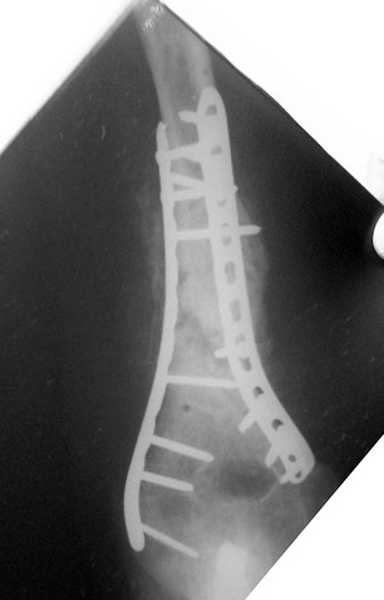

На примере два случая, извиняюсь за качество снимков, снимки и случаи из бывшего союза.

Первая больная с "успехом" была прооперирована 6 раз различными методами открытого и закрытого

остеосинтеза, включая то, что в Кисловодске заезжим австралийским "кудесником" на ложный сустав уложена скорлупа от страусиновых яиц. Последняя операция одиноким локинг плейт в одной из клиник.

Через год по поводу тех же проблем сделали ревизию, оригинальную пластину оставили как есть, только укрепили добавлением еще одной пластины и сделали костную пластику.

Через два месяца увидели признаки консолидации.